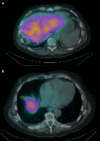

Figure 5

Figure 5. Bremstralung scan after the treatment at the level of the upper abdomen (a) and lower chest (b) demonstrating no activity in the previously seen areas.